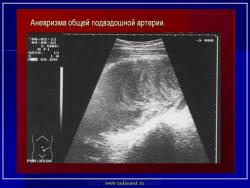

УЗИ  аорты.